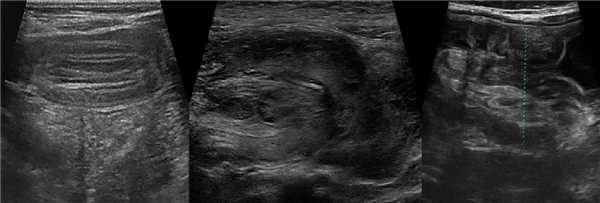

Рисунок. Мальчик 7-ми лет поступил в больницу с резкой приступообразной болью в животе и рвотой. На УЗИ в брюшной полости определяется цилиндрическая слоистая масса — гипо- и гиперэхогенные структуры чередуются. На продольном срезе (1) хорошо видно влагалище и головку инвагината, которая покрыта гиперэхогенной «шапочкой» испражнений. На поперечных срезах (2, 3) четко прослеживается гипоэхогенные внешний и внутренний цилиндры тела инвагината, промеж них гиперхогенный жир брыжейки с гипоэхогенными «бусинами» лимфоузлов (3). Лимфоузлы брыжейки увеличены (4). Заключение: Эхо-признаки инвагинации кишечника. Мезаденит.

Рисунок. Женщина 55-ти лет на протяжении 2-х недель жалуется на боль в животе. На УЗИ внизу живота слева определяется слоистая структура протяженностью 3 см (1), на поперечных срезах похожа на «мишень» (2) и «бублик» (3, 4). Заключение: Эхо-признаки инвагинации кишечника. Через 6 часов на КТ петли тонкой кишки несколько отёчны, другой патологии не выявлено. Обратите внимание, короткие кишечные инвагинаты могут расправляться самопроизвольно, поэтому пациента следует наблюдать некоторое время.

Рисунок. Девочка в возрасте 10-ти месяцев поступила в больницу с резкой приступообразной болью в животе, кал с кровью. На УЗИ в брюшной полости определяется цилиндрическая масса с гиперэхогенным центром и гипоэхогенной периферией — «псевдопочка». На поперечных срезах образование походит на «бублик»; можно рассмотреть гипоэхогенные внешний и внутренний цилиндр тела инвагината, а так же гиперэхогенный жир брыжейки с округлыми лимфоузлами. При ЦДК в сосудах брыжейки определяется кровоток. Заключение: Эхо-признаки инвагинации кишечника.

Рисунок. Мальчик в возрасте 6-ти месяцев поступил в больницу с болью в животе, рвотой и кровавыми испражнениями. На УЗИ под печенью определяется цилиндрическое слоистое образование (длина 40 мм, диаметр 30 мм) и небольшое количество свободной жидкости (4). Заключение: Эхо-признаки инвагинации кишечника.

Рисунок. Мальчик 4-х лет с жалобами на внезапную сильную боль в животе. Внизу живота справа определяется слоистая цилиндрическая масса, в структуре которой хорошо видно гиперэхогенный жир брыжейки с округлыми гипоэхогенными лимфоузлами. Заключение: Эхо-признаки инвагинации кишечника.